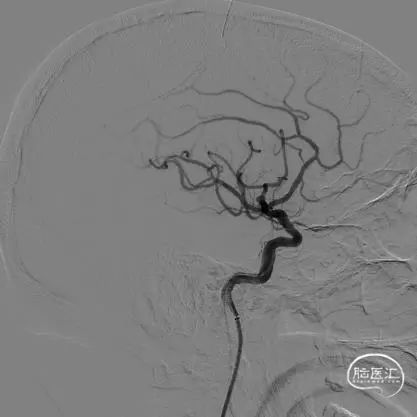

栓塞微导管及支架微导管到位后,首先使用弹簧圈2*3一枚试行成篮。由于瘤颈太宽,弹簧圈溢出动脉瘤。故部分释放弹簧圈后,先行完全释放支架,再继续释放弹簧圈栓塞。

术中可见Atlas支架定位精准,支架释放过程中,栓塞导管没有受到任何影响,待支架完全打开后,将首枚弹簧圈全部释放。

经SL-10微导管送入1.5*3弹簧圈进行填塞,可见部分弹簧圈突入支架与瘤颈处的载瘤动脉之间。突出的弹簧圈形成基座,确保瘤颈处得到栓塞而不复发。

继续使用1.5*2、1*1两枚弹簧圈收尾。可见Atlas支架网眼较小,完全可以阻挡小弹簧圈通过网眼进入载瘤动脉。